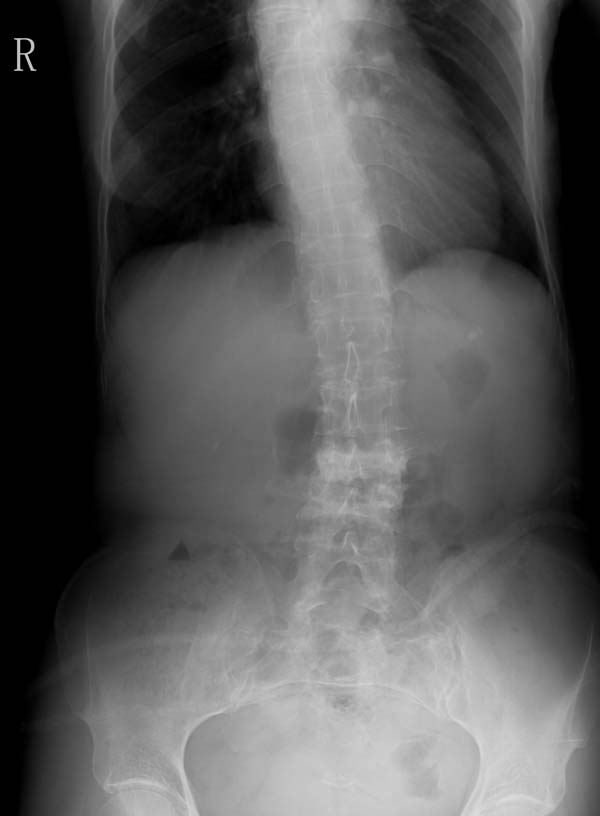

以下是引用hhcckk在2007-7-27 17:40:00的发言:[br]l3、4椎体压缩变扁,椎间隙增宽,考虑转移瘤可能性大[br]1、结核一般多有椎间隙的狭窄(当然中央型的可无椎间隙的狭窄,但毕竟少见,而且到后期也会累及椎间隙),椎旁的寒性脓肿,好发年轻人,好发于胸椎,临床有结核中毒症状,种种征象都不太支持[br]2、骨软骨炎、嗜酸性肉牙肿可以使椎体压缩变扁,椎间隙无狭窄,甚至可以增宽,但这两种病多好发于年轻人,年纪大的还是首先排除转移性肿瘤再考虑其它的疾病吧

以下是引用听蝉观竹在2007-7-28 21:05:00的发言:[br]这个病例有几个影像特点:1、病变为2个腰椎椎体,2、椎体有明显和压缩,密度明显增高,第4腰椎椎体见皮质破坏;2、椎间隙无狭窄,而且变宽。[br]分析:[br]1、上述影像改变不符合脊椎结核,因为脊椎结核主要病变是先累及椎体边缘软骨和椎间盘,所以象x线表现主要的改变是-------椎间隙变窄和椎体边缘的破坏。而本病例恰恰相反------椎间隙无狭窄,而且变宽。[br][br]2、这个病例符合脊椎转移性骨肿瘤的表现-----多个椎体的的破坏和病理压缩性骨折、椎间隙无狭窄,而且变宽。[br][br]3、女性,60岁,又普遍存在骨质疏松,应该注意与骨质疏松的压缩骨折向鉴别。对这个病例我分析-----(1)[br]病变是在腰3、4椎体,而不是胸12、腰1椎体,不符合压缩骨折的受力特点;(2)第4腰椎椎体见明确骨皮质破坏。所以我考虑转移性骨肿瘤可能性要远大于骨质疏松的引起的压缩骨折。[br][br]4、老年女性,脊椎转移性骨肿瘤,寻找原发肿瘤首先应该查乳腺、甲状腺、生殖腺。[br]